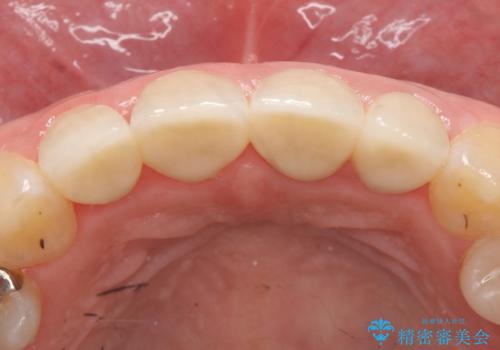

左上1、2の再根管治療終了後、オールセラミッククラウン(スペシャル)による補綴を行いました。

前歯の補綴ではオールセラミッククラウンを希望される患者様が多いですが、オールセラミッククラウンの中でも、エコノミー、スタンダード、スペシャル、エクセレントとランクがあります。

その中でも特に審美性が高いのがスペシャル、エクセレントです。スペシャル、エクセレントは口腔内写真をもとに熟練の技工士が、患者様の口腔内に合わせたオーダーメイドのクラウンを製作致します。